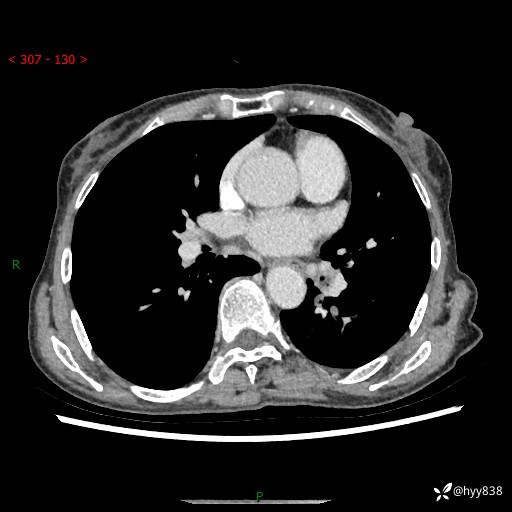

胸部CT平扫+增强